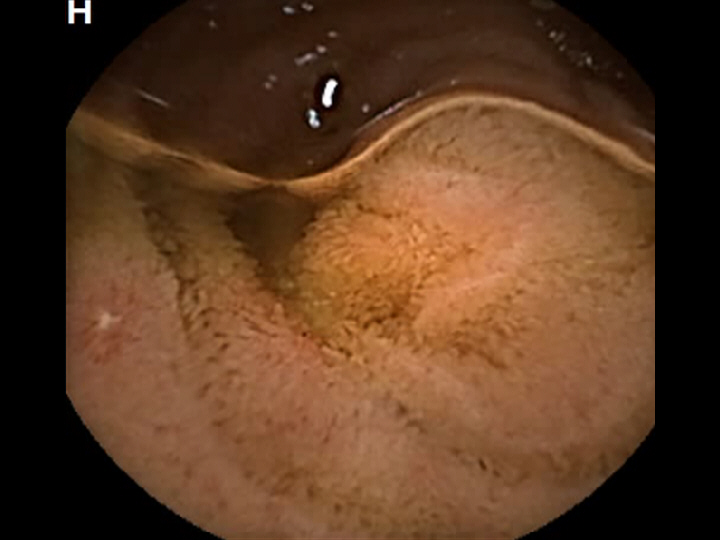

CAPSULE ENDOSCOPY: Crohns Disease: Aphthous Ulcerations in the Small Bowel

Crohns Disease: Aphthous Ulcerations in the Small Bowel. Just click on a picture!

Crohns Disease: Aphthous Ulcerations in the Small Bowel